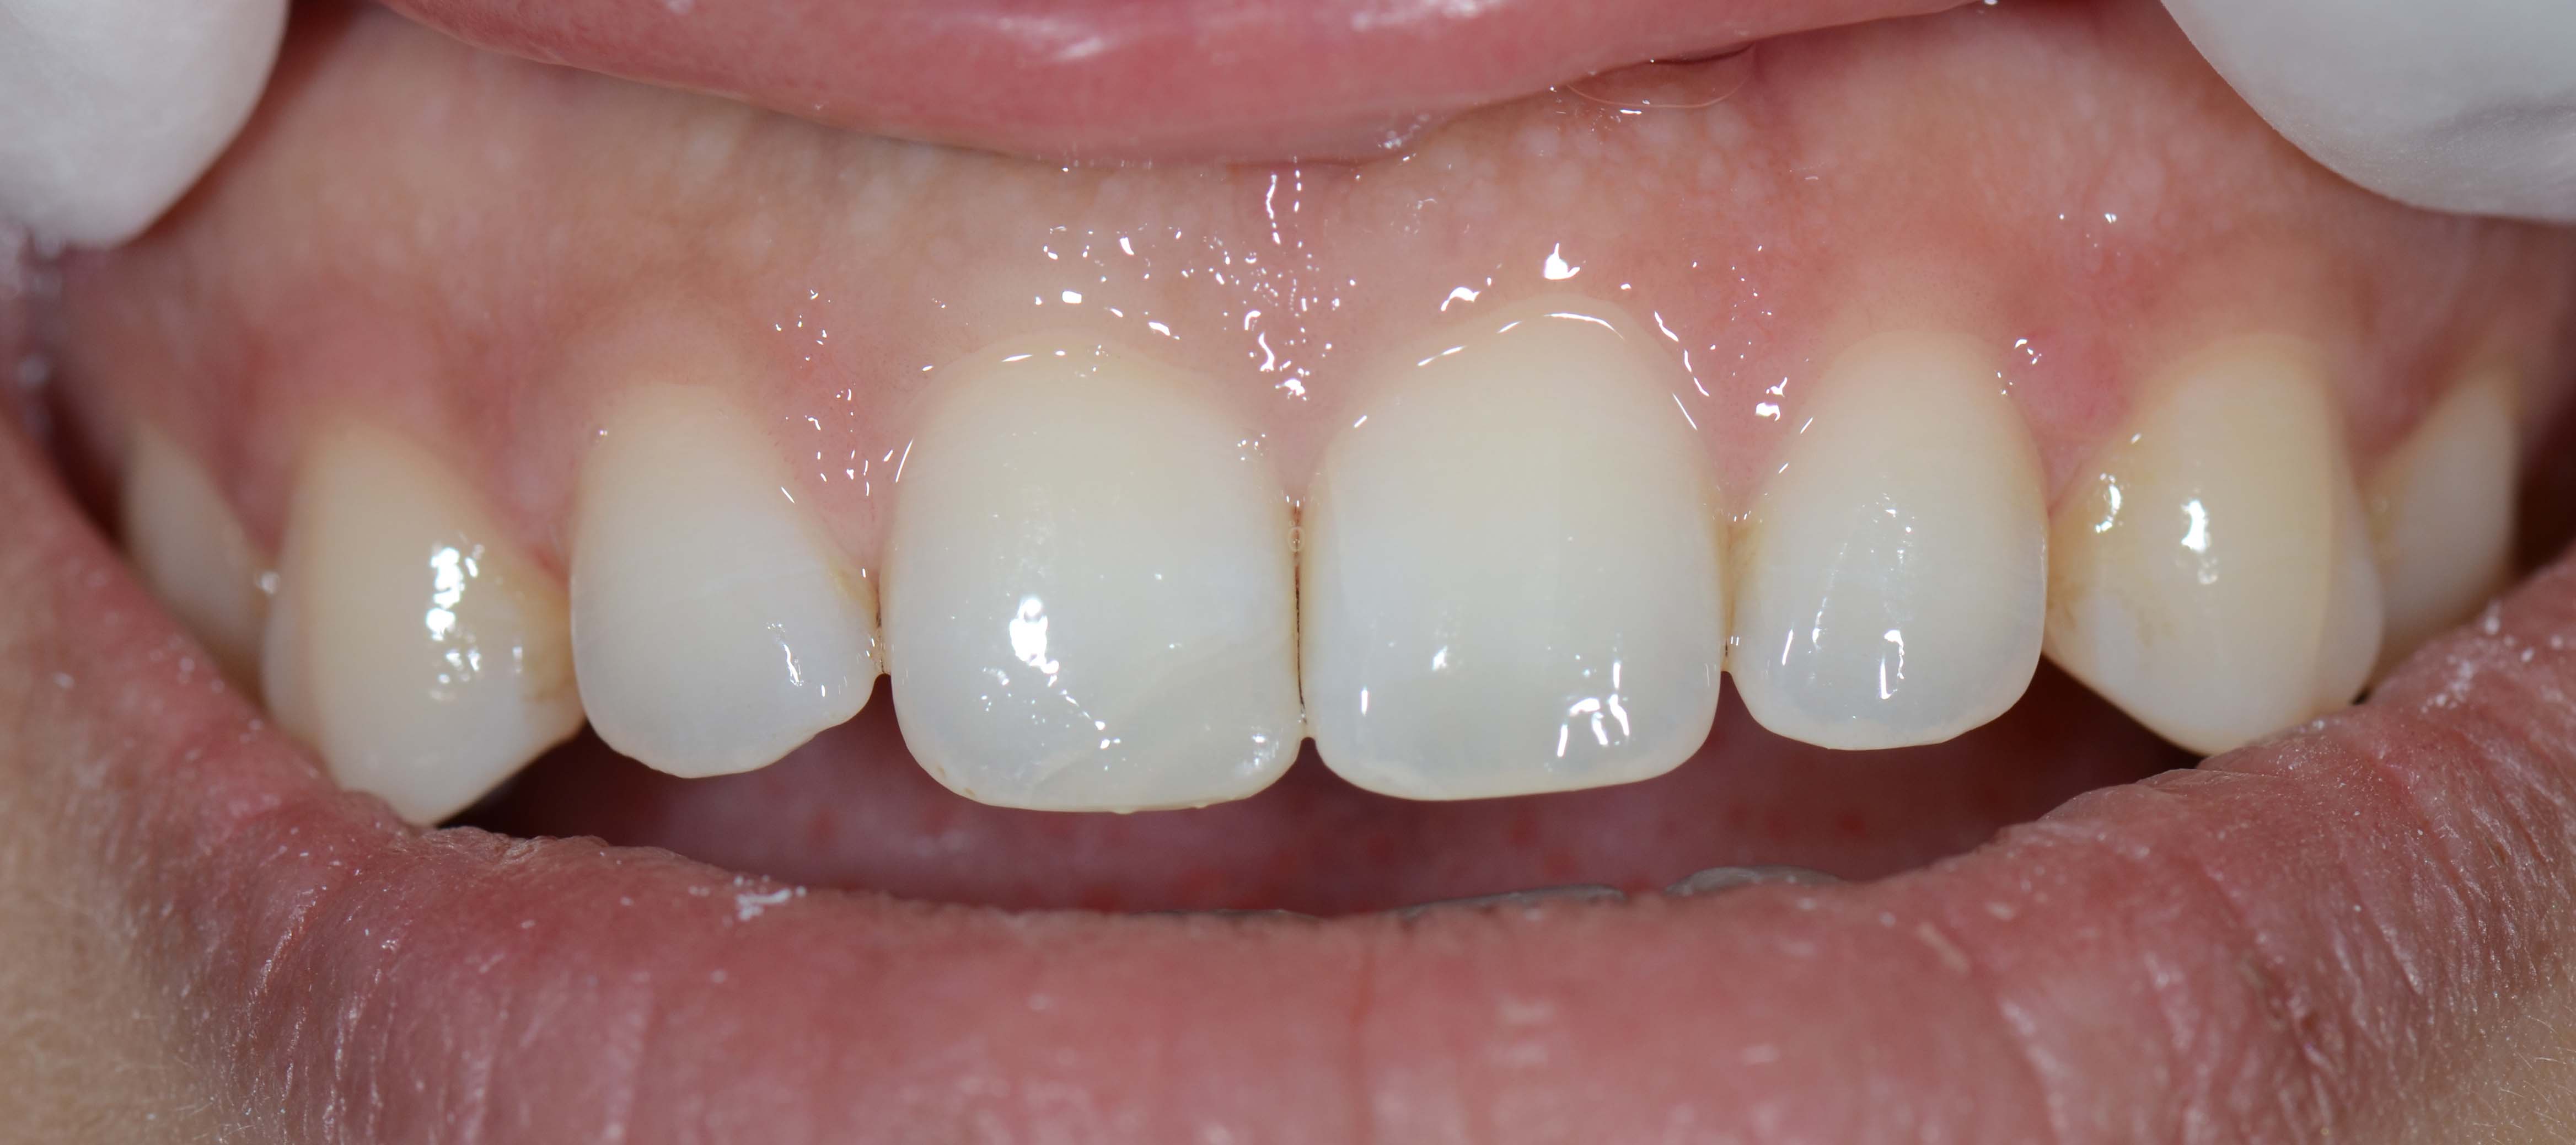

• Photos

Urgent treatments are executed if necessary as in the case on the left.